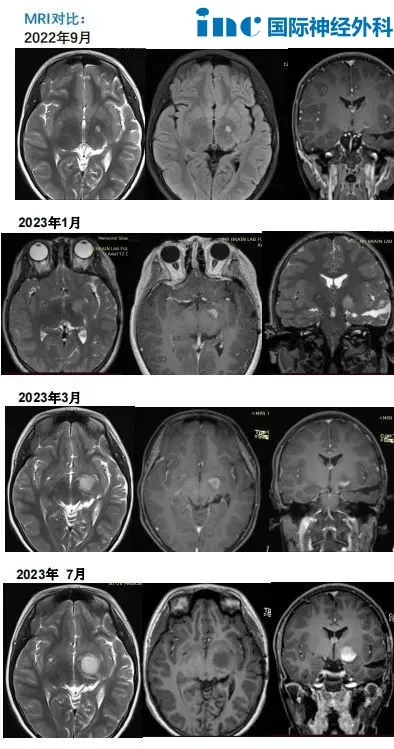

Rutka教授案例分享:下丘脑胶质瘤,三年内复发

2020年,11岁女孩Judy出现整整1年的发育迟缓,父母带着Judy去看儿科医生,对于身高停止增长的问题,儿科医生建议她做脑部CT,问题果然出在脑袋上:医生在Judy脑袋的左侧鞍旁发现了占位性病变。

手术治疗后病理结果显示:毛细胞型星形细胞瘤,WHO I级。术后Judy定期接受核磁共振对比检查,但却出现了视野缺损,且没有任何好转。

术后MRI对比

2022年,复查MRI发现左侧丘脑微小异常信号,手术医生建议服用靶向药物或化疗,但当时没有采取任何治疗措施,只是继续通过复查核磁共振进行观察。

2023年,再次复查MRI显示病灶明显增大,于是他们再次咨询了之前的手术医生。医生还是建议服用靶向药物。但是,靶向治疗3个月后复查MRI显示病灶进一步增大和强化。

于是Judy父母远程咨询了INC国际神经外科专家团成员Rutka教授,Rutka教授为孩子的病情做了详细的评估,并为Judy进行了LITT手术。